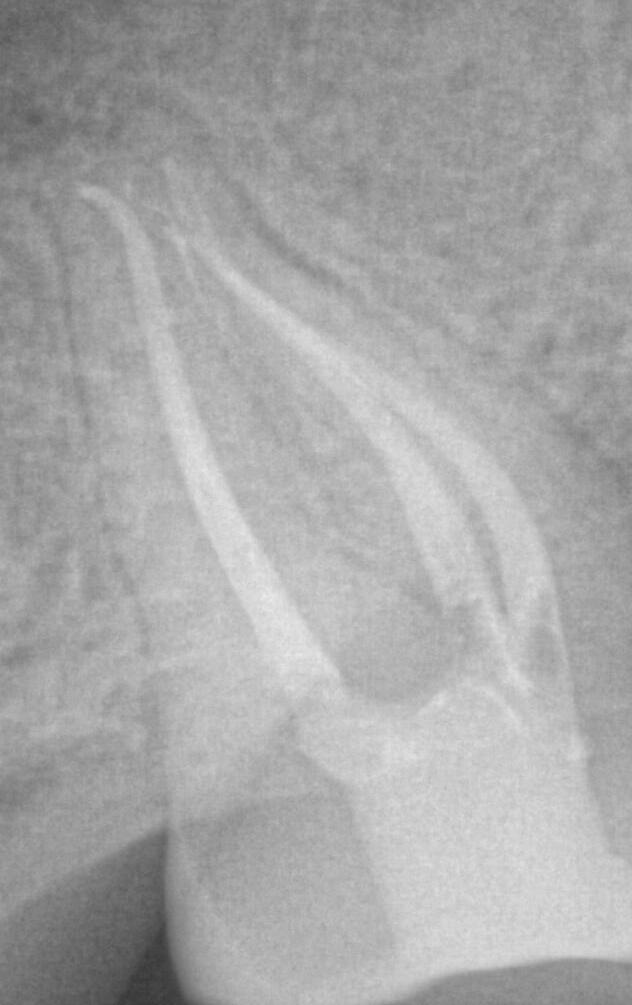

We are proud to announce that we have partnered with Zarc4Endo, a company founded and operated by Endodontists for Endodontists to bring Avalon Biomed by Zarc, with a portfolio of innovative endodontic file families, corresponding gutta percha and paper points, cordless devices, and accessories, to the U.S market. Based out of Madrid Spain, Zarc launched BlueShaper, the world’s first pink & blue dual alloy system in January 2021. Behind the scenes, over the past year our KOLs across the U.S. have been using this first of its kind file system with performance and quality exceeding all of their expectations.